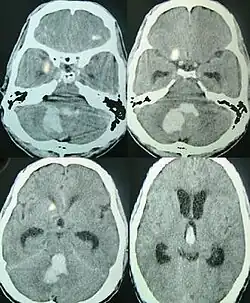

Tanto a angiografia por tomografia computadorizada (ATC) como a angiografia por ressonância magnética (ARM) demonstraram ser efetivas no diagnóstico de malformações vasculares intracranianas após a hemorragia intracerebral.[13] Com tanta frequência, um angiograma de tomografia computadorizada será realizado para excluir uma causa secundária de hemorragia[14] ou para detectar um "sinal local".

A hemorragia intraparenquimatosa pode ser reconhecida na tomografia computadorizada porque o sangue aparece mais brilhante do que outro tecido e é separado da mesa interna do crânio por tecido cerebral. O tecido que envolve um sangramento é muitas vezes menos denso do que o resto do cérebro por causa do edema e, portanto, aparece mais escuro na tomografia computadorizada.[14]

Quando devido à pressão arterial elevada, eles geralmente ocorrem no putâmen ou no tálamo (60%), no cérebro (20%), no cerebelo (13) ou na ponte (7%).[15]